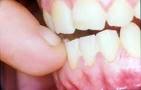

R.R.I. (Reabsorciòn radicular interna) dentro de los factores etiológicos encontramos Caries Trauma dentoalveolar Blanqueamiento dental agresivo Tratamiento de conductos Dientes reimplantados

R.R.E (Reabsorción radicular externa): Es idiopática y su etiología

es asociada a Traumatismos mecánicos agudos o crónicos. Dientes impactados,

Procesos inflamatorios pulpares ,Procesos inflamatorios periodontales.

Interna:

En el interior de la cavidad

pulpar se da un cambio distrofico idiopático por

trauma o preparación inadecuada de una cavidad, se desarrolla a través de una hemorragia

que produce destrucción de dentina. A su vez se clasifica en:

· Externa:

Inicia por estimulo

externo del ligamento periodontal y avanza de cemento a dentina.